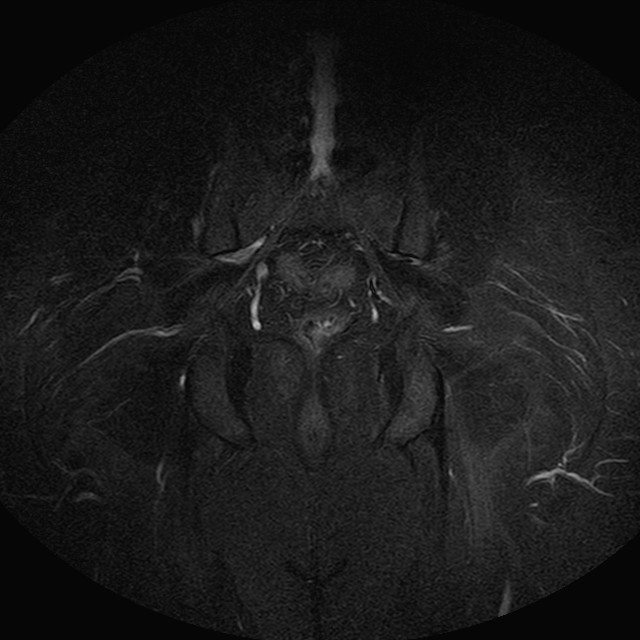

eSTIR

Evidenti e simmetriche alterazioni osteofitosiche in regione coxo femorale con riduzione delle rime articolari. Degenerazione completa del cercine glenoideo. Non attuali segni di versamento articolare. Non segni di edema osseo che escludono attuale algodistrofia od osteonecrosi. Lieve e simmetrica riduzione del trofismo della muscolatura glutea.